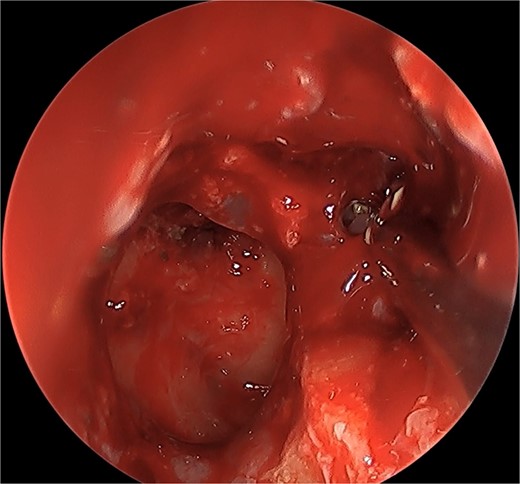

We present a case of a 52-year-old female, not known to have any chronic disease, who presented to our institution’s otorhinolaryngology clinic with a complaint of headache, facial pain, and PND for 6 months. Endonasal endoscopic examination was unremarkable. A paranasal sinus CT was requested to aid the diagnosis, which showed two simultaneous opacities occupying the left maxillary and right sphenoid sinuses, respectively (Fig. 1A and B). The opacified lesions were associated with calcifications, metallic shadowing, and bony thickening of the sinus wall. According to the history and radiological imaging findings, a diagnosis of a fungal ball occupying both the maxillary and sphenoid sinuses was achieved, and a functional endoscopic sinus surgery (FESS) with left wide maxillary antrostomy removal of the thick fungal debris occupying the left maxillary sinus (Fig. 2) was decided to be performed. In addition, a wide endoscopic sphenoidotomy was performed, and the sphenoid sinus was full of fungal debris (Fig. 3), which was cleaned thoroughly. The patient had an uneventful post-operative course.

Post-operative endoscopic view post sphenoidectomy and maxillary antrostomy.